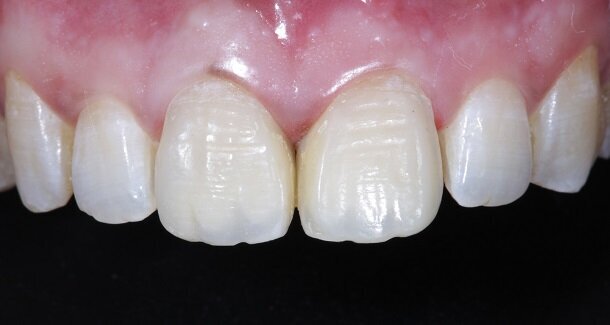

Presenting a case of a 22 yr old male, who reported to our dental office with fractured Maxillary Central incisors many years ago [Figures 1 and 2]. On examination both Maxillary Central incisors had fractures with pulp exposures. IOPAR showed large peri-apical lesions in both teeth. There was no mobility seen in either teeth, but discolouration was seen in both. Non-surgical Endodontic treatment followed by Bleaching and Direct composite restorations (2 weeks post bleaching) were planned.

The figures show the clinical work flow involved. In the 1st appointment Oral prophylaxis, oral hygiene instructions were followed by an impression that was sent to the lab for a wax up [Fig 3 and 4]. In the subsequent appointments, Endodontic treatment was followed by Intra and extra coronal office bleaching using the Pola office bleaching kit. After two weeks, the shade stabilised post bleaching. Shade selection, rubber dam isolation and preparation was done on both the teeth to receive Direct composite veneers so as to close the midline diastema as well as correct the fractured teeth and the slight mal-alignment. Controlled Body Thickness (CBT) technique of layering was used with 3M Z350XT shades - Dentin shades A3, A2 and Enamel shades A2, clear translucent [Figures 5 to 11]. This was followed by the Finishing and polishing protocol as described in the figures.